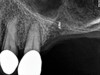

The implant is then delivered and should be well stabilized in the bone. If there is any mobility of the implant, it can either be placed a little deeper (if there is enough native bone) or the implant can be removed and the procedure aborted, in which case it would be a two-stage procedure. This should rarely occur with the tapered designed implant, even with only 2 mm of native bone. Using a bone-level platform-shifting implant (or a tissue-level designed implant) is critical, as the hard and soft tissue will establish a biologic width. If an external hex type of implant is used and the shoulder is placed at the bone level, an expected bone loss of 1.5 mm to 2 mm will occur.24 Figure 10 shows proper bone-level implant depth placement with a platform-shifting design. In this case, a 3-mm healing abutment was placed at the time of surgery to avoid a secondary uncovering surgery, but an implant-level healing abutment could have been placed instead. As can be seen, there was only about 2 mm to 3 mm of native bone height. The membrane was raised about 8 mm to 9 mm. Comparing the radiograph on the day of surgery (Figure 10) to the 6-month postoperative radiograph (Figure 11) shows no loss of native bone, as well as the positive change in appearance of the grafted bone. The 3.5-month CBCT scan (Figure 12) shows good healing of the bone with no coronal bone loss. With minimal native bone present, as in this case, the use of a non-platform-shifting or non-tissue-level implant design could be problematic. After 1.5 mm to 2 mm of crestal bone loss, an external hex designed implant could develop instability with possible implant failure. If a non-tapered implant is used and bone loss occurs during healing, migration of the implant into the sinus could potentially occur. The surgeon can use either a healing abutment or implant-level closure screw over the implant shoulder. With patients who tend to use their tongues to explore or play with the area, or if the area is under a removable partial denture, a closure screw is recommended.

Fig 11. 7-month postoperative radiograph of the restored implant No. 3.

Figure 11